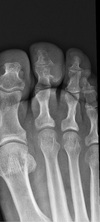

4

5

7

Q

What is the most common malignancy of bone?